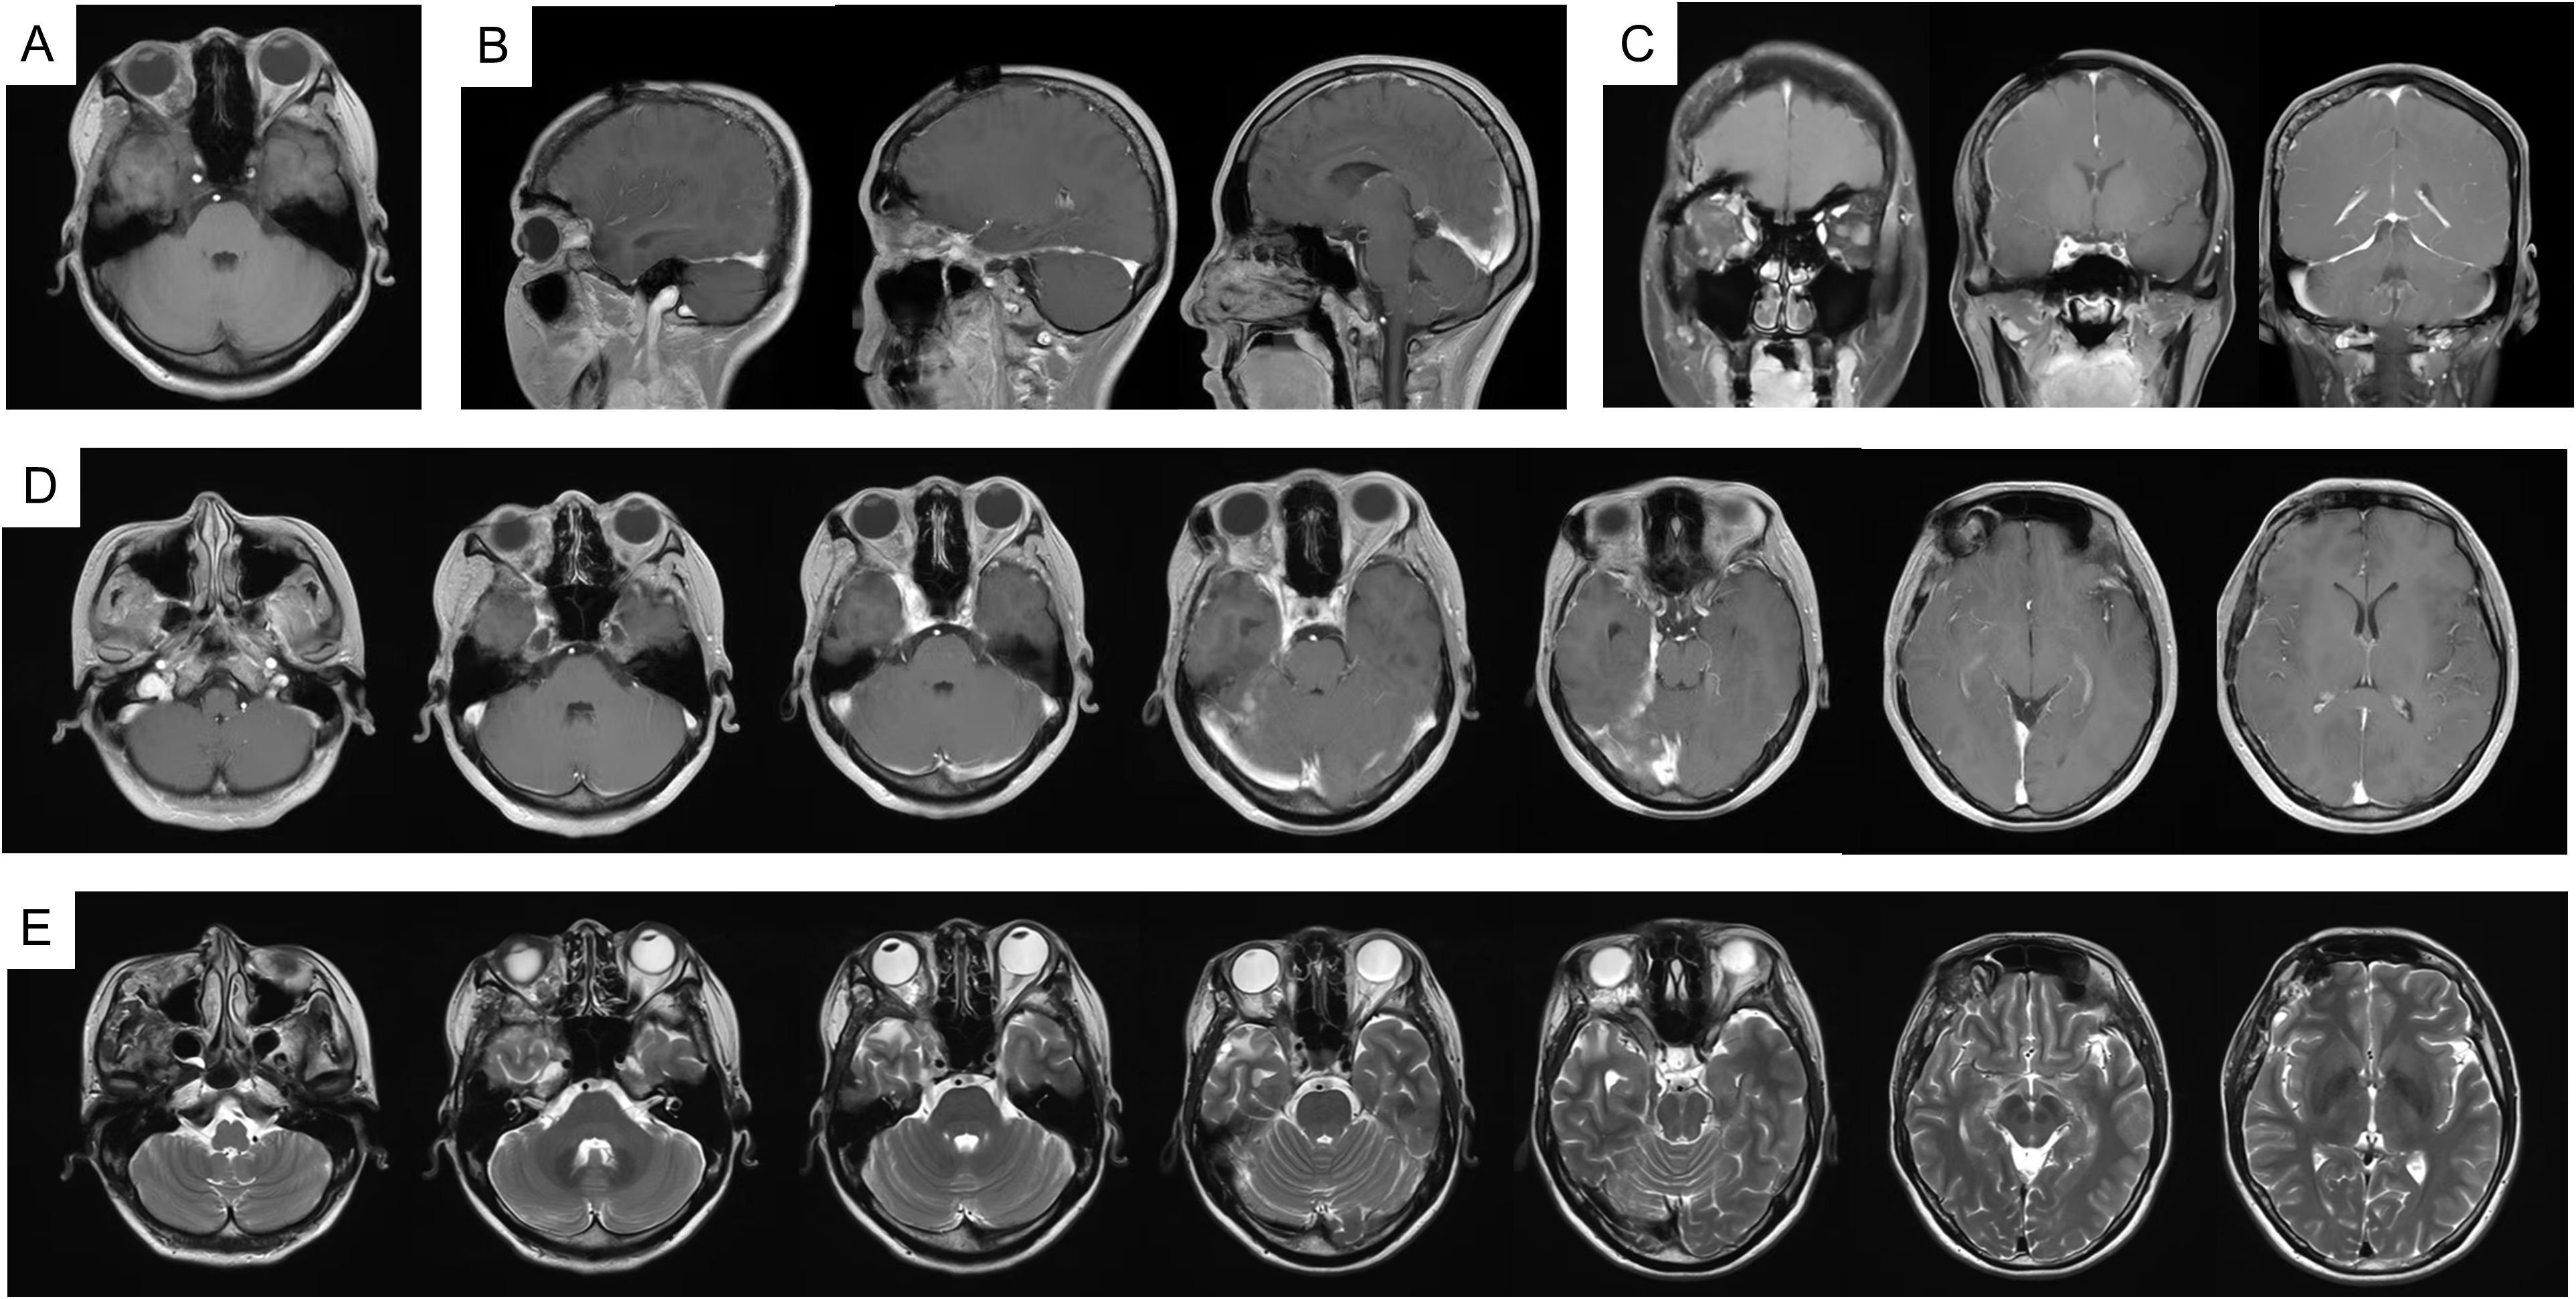

In 2023, due to worsening symptoms and brainstem compression (Figure 1), palliative surgical resection was performed. Multiple tumor nodules beneath the temporal muscle and intraorbital lesions were partially removed. Postoperative histopathological analysis confirmed the diagnosis of hemangioma, characterized by dilated vascular channels lined by a single layer of endothelial cells without atypia, consistent with a cavernous subtype. This pathological confirmation established the final diagnosis, thereby excluding other radiologically plausible differential diagnoses such as meningioma (which typically shows dural attachment and uniform enhancement), schwannoma (which often arises from cranial nerves with distinct borders), or arteriovenous malformation/hemangioblastoma (usually associated with flow voids or feeding vessels). At four months post-surgery, follow-up MRI (Figure 2) showed partial improvement of right cerebral edema, though a substantial intracranial tumor burden persisted.

Figure 1

Figure 1. MRI imaging in 2023. (A) T1WI; (B) T1WI-C coronal view; (C) T1WI-C sagittal view; (D) T2WI-TSE. MRI, magnetic resonance imaging; T1WI, T1-weighted image; T2WI, T2-weighted image; T1WI-C, T1WI with contrast; T2-FLAIR, T2-fluid attenuated inversion recovery.